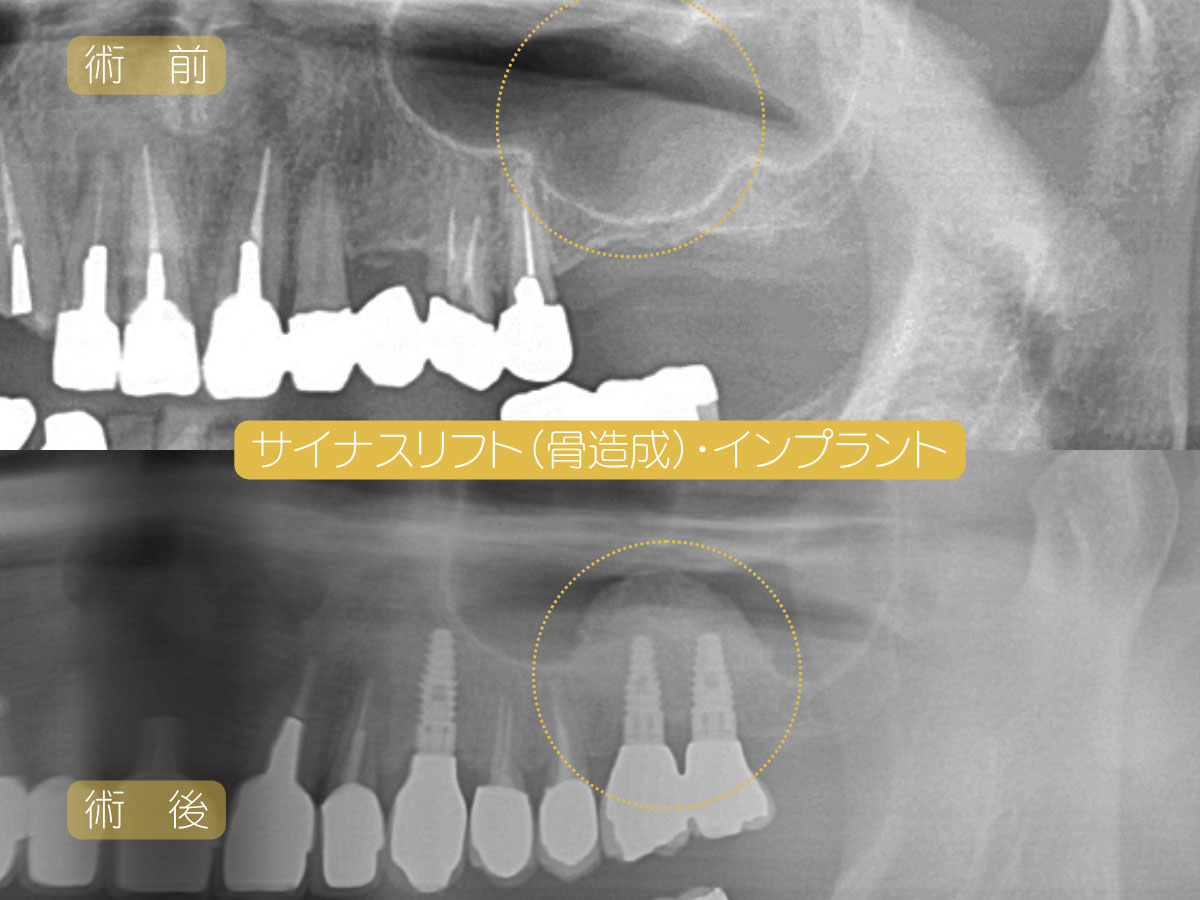

●サイナスリフト

上あごの骨が少ない場合に行う手術です。上あごの奥歯の上方には「上顎洞」(サイナス)という空洞があります。この空洞に補填材(骨と同様の組成で最終的に自家骨に置き換わっていくもの)を填入することで、骨を作ります。